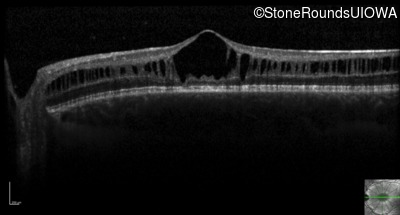

Optical Coherence Tomography - Left - 20/50 -2

Exemplar / OCT Stack